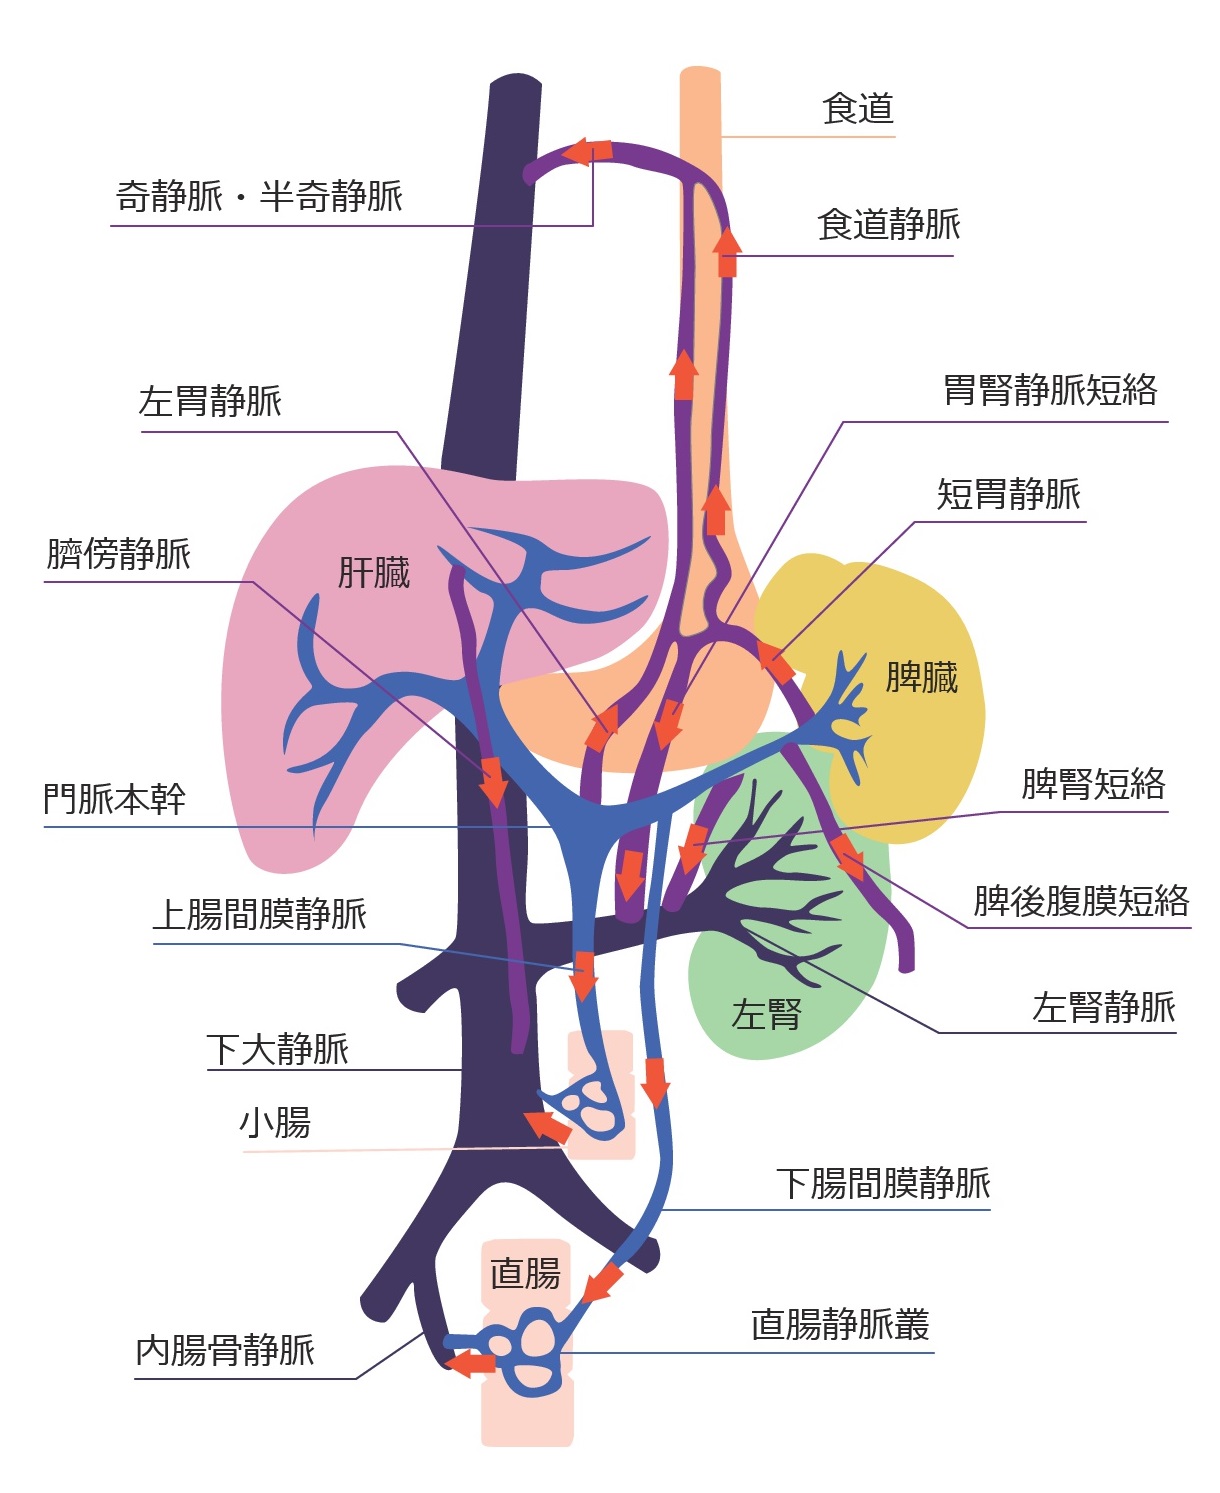

診療内容 食道癌 神戸大学大学院医学研究科外科学講座 食道胃腸外科学分野